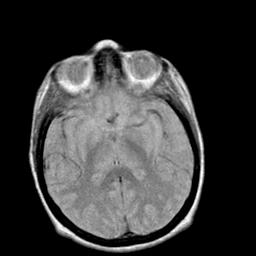

Creutzfeld-Jakob disease: proton density-weighted MR -- Slice #12

[Home][Help][Clinical] Slice 12